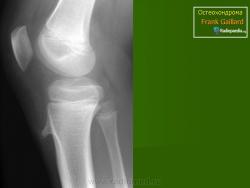

Локализация остеохондромы: частота поражения отдельных костей различна; нижний коней бедренной кости, верхние отделы плечевой и большеберцовой костей поражаются более чем у половины больных. На всем протяжении остеохондрома покрыта надкостницей. Она может быть обнаружена и в других костях, за исключением костей лицевого черепа. Все же поражение костей позвоночника, кистей рук и стоп встречается редко. При рентгенологическом исследовании видна типичная картина узкого или широкого выроста вблизи эпифизарной части пораженной кости. Обычно плотность узла неоднородная, имеются многочисленные плотные участки, соответствующие обызвествленным хрящевым долькам. Хрящевая «шапочка» большей частью не определяется, поскольку хрящ остается необызвествленным. Она может быть выявлена только при магнитно-резонансной томографии.